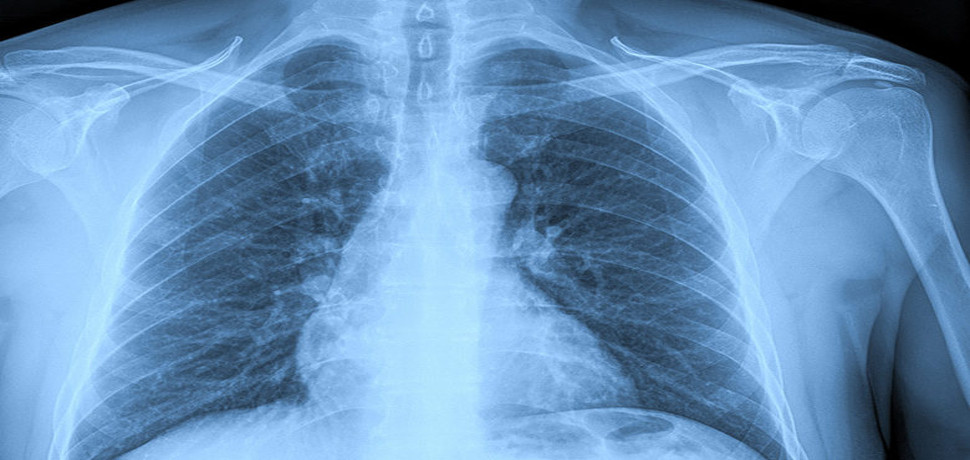

• ακτινογραφία θώρακος

Η ψηφιακή ακτινογραφία (digital radiography-digital x-rays) είναι ότι πιο εξελιγμένο υπάρχει σήμερα στον τομέα της ακτινογραφίας με τη μικρότερη δυνατή δόση ακτινοβολίας για τον άρρωστο.

Με την ψηφιακή ακτινογραφία σε πραγματικό χρόνο βλέπουμε την ακτινογραφία στην οθόνη του υπολογιστή μας δίπλα στον ασθενή και μπορούμε να πετύχουμε το βέλτιστο αποτέλεσμα απεικόνισης.